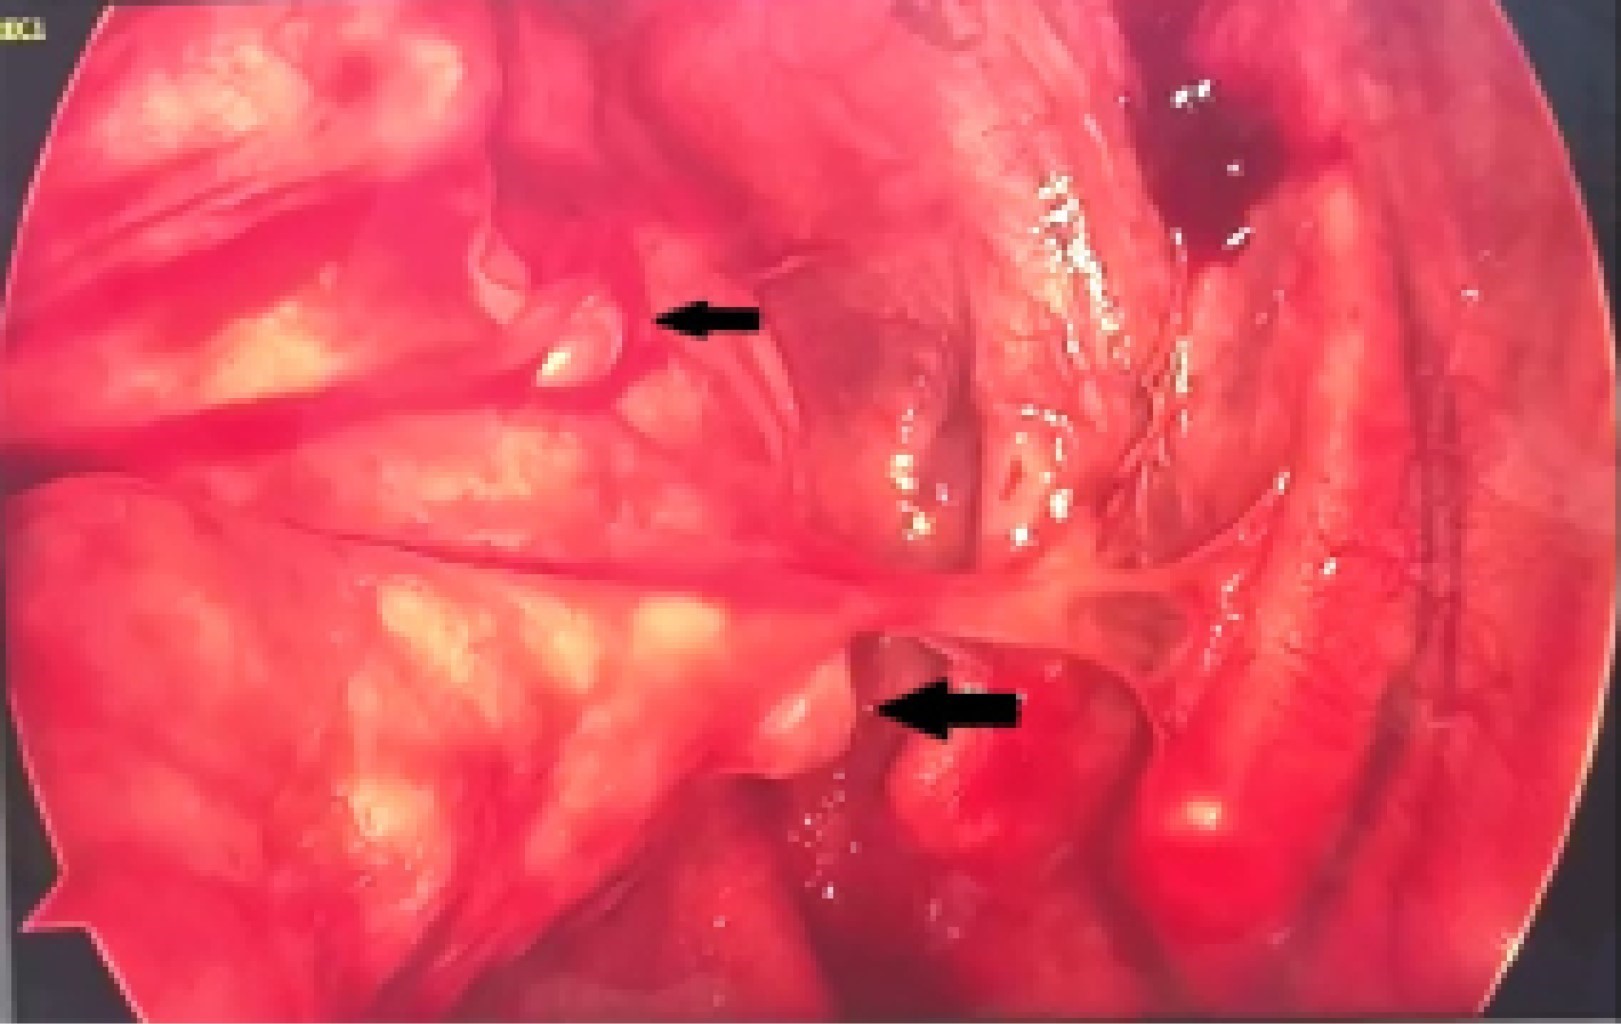

Thoracoscopy was performed on 11/03/21, finding lax adhesions in the pulmonary apex to the thoracic wall and two bullae in the left apical lobe of approximately 0.5-1 cm (Figure 5). A bullectomy was performed without complications and an endo pleural suction tube was left in place (Figure 6).

Figure 5